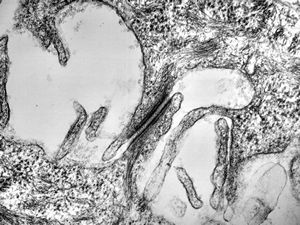

M,41y. | ribosome-lamella complex in tricholeukocyte -hairy cell leukemia, spleen